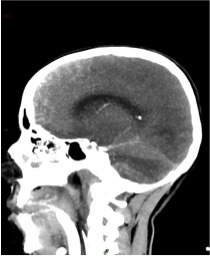

Un angioscanner est donc réalisé, dont voici les reconstructions en coupe axiale et sagittale :

Question 13 : Cet angioscanner présente :

Le diagnostic de mort encéphalique en angioscanner, selon les recommandations de la Société Française de Neuroradiologie, repose sur :

l’absence d’opacification des veines profondes (veines cérébrales internes (Figure 24 flèches marrons) et grande veine cérébrale (Figure 25 flèche jaune)

l’absence d’opacification bilatérale des branches corticales des artères cérébrales moyennes (Figure 24 flèches bleues). (En complément, sur la Figure 25, flèche orange : les artères péricalleuses qui sont des branches issues des artères cérébrales antérieures).